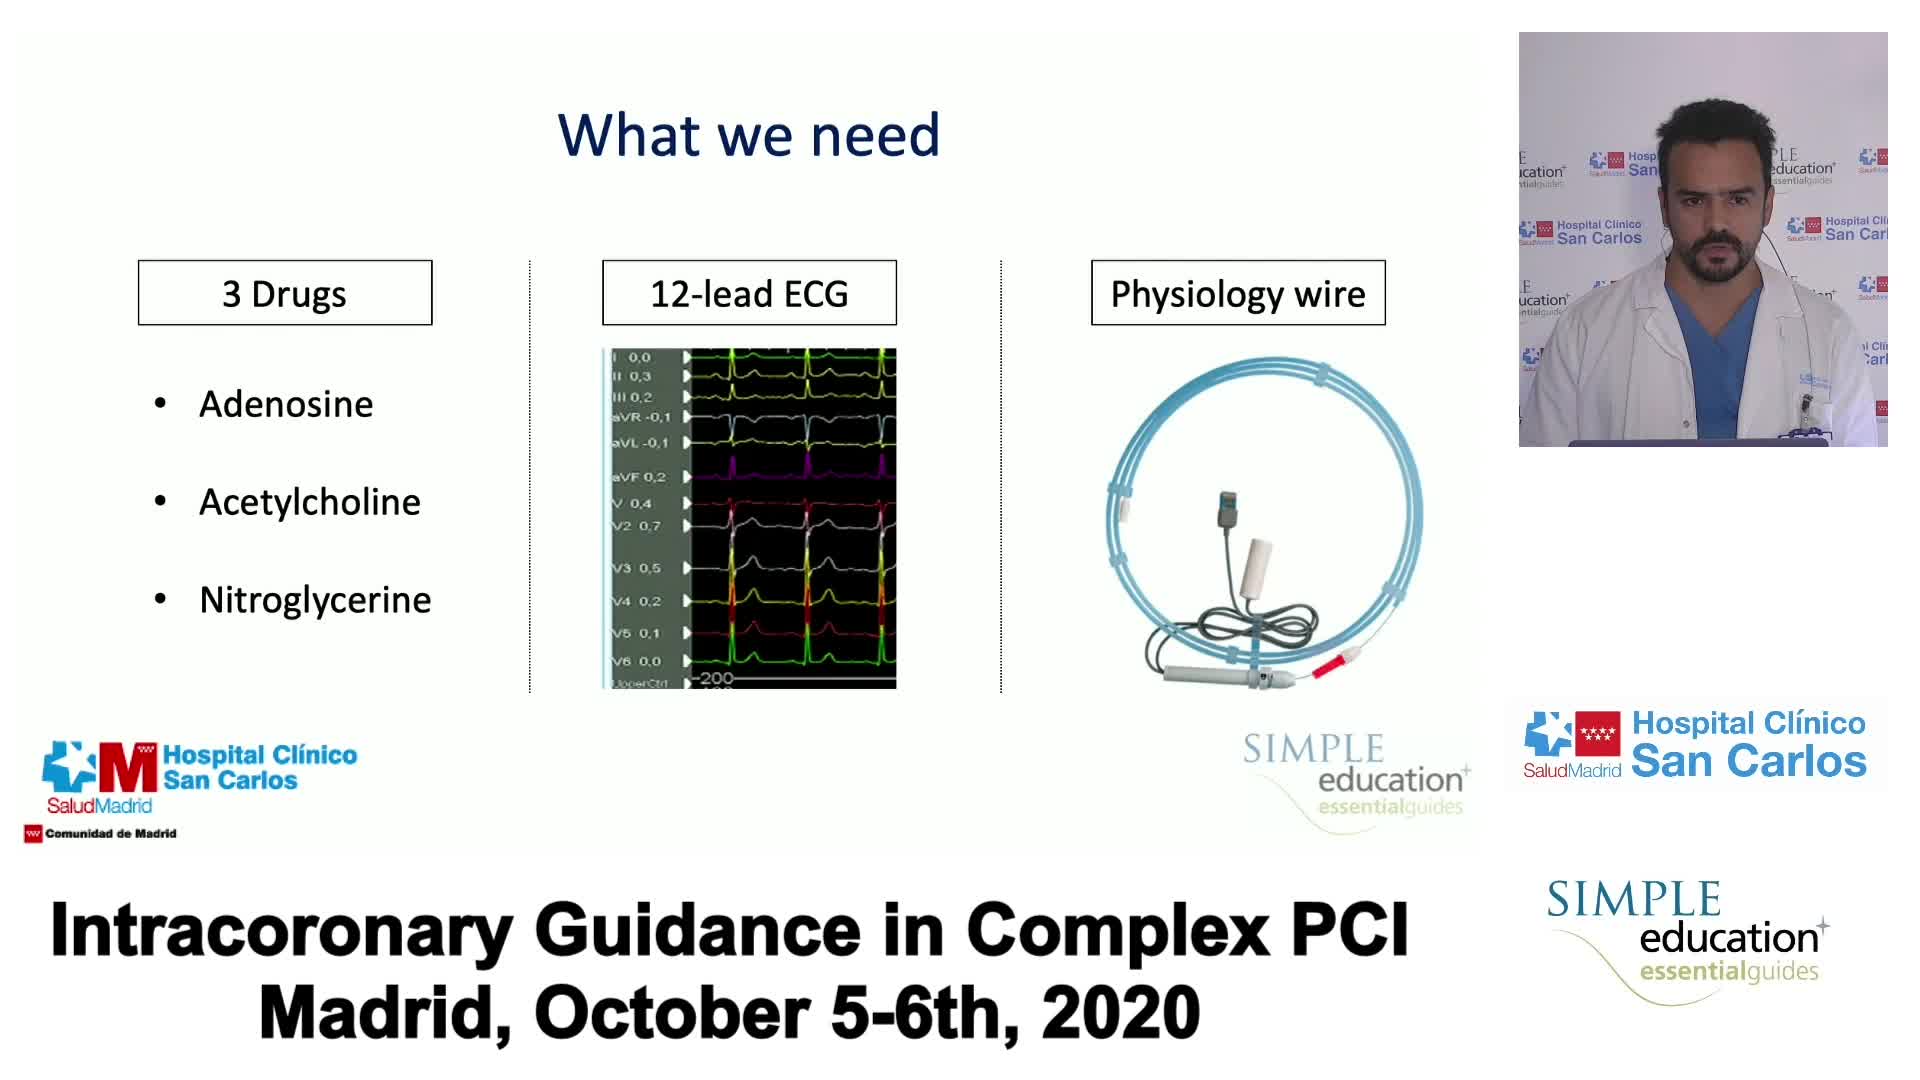

Why is the physiology negative? Integration of the coronary microcirculation to decision-making

Understanding mechanisms of regulation of resting and hyperaemic blood flow, across single and serial stenoses

Intracoronary guidance in acute coronary syndromes - Dr Hernan Mejia-Renteria